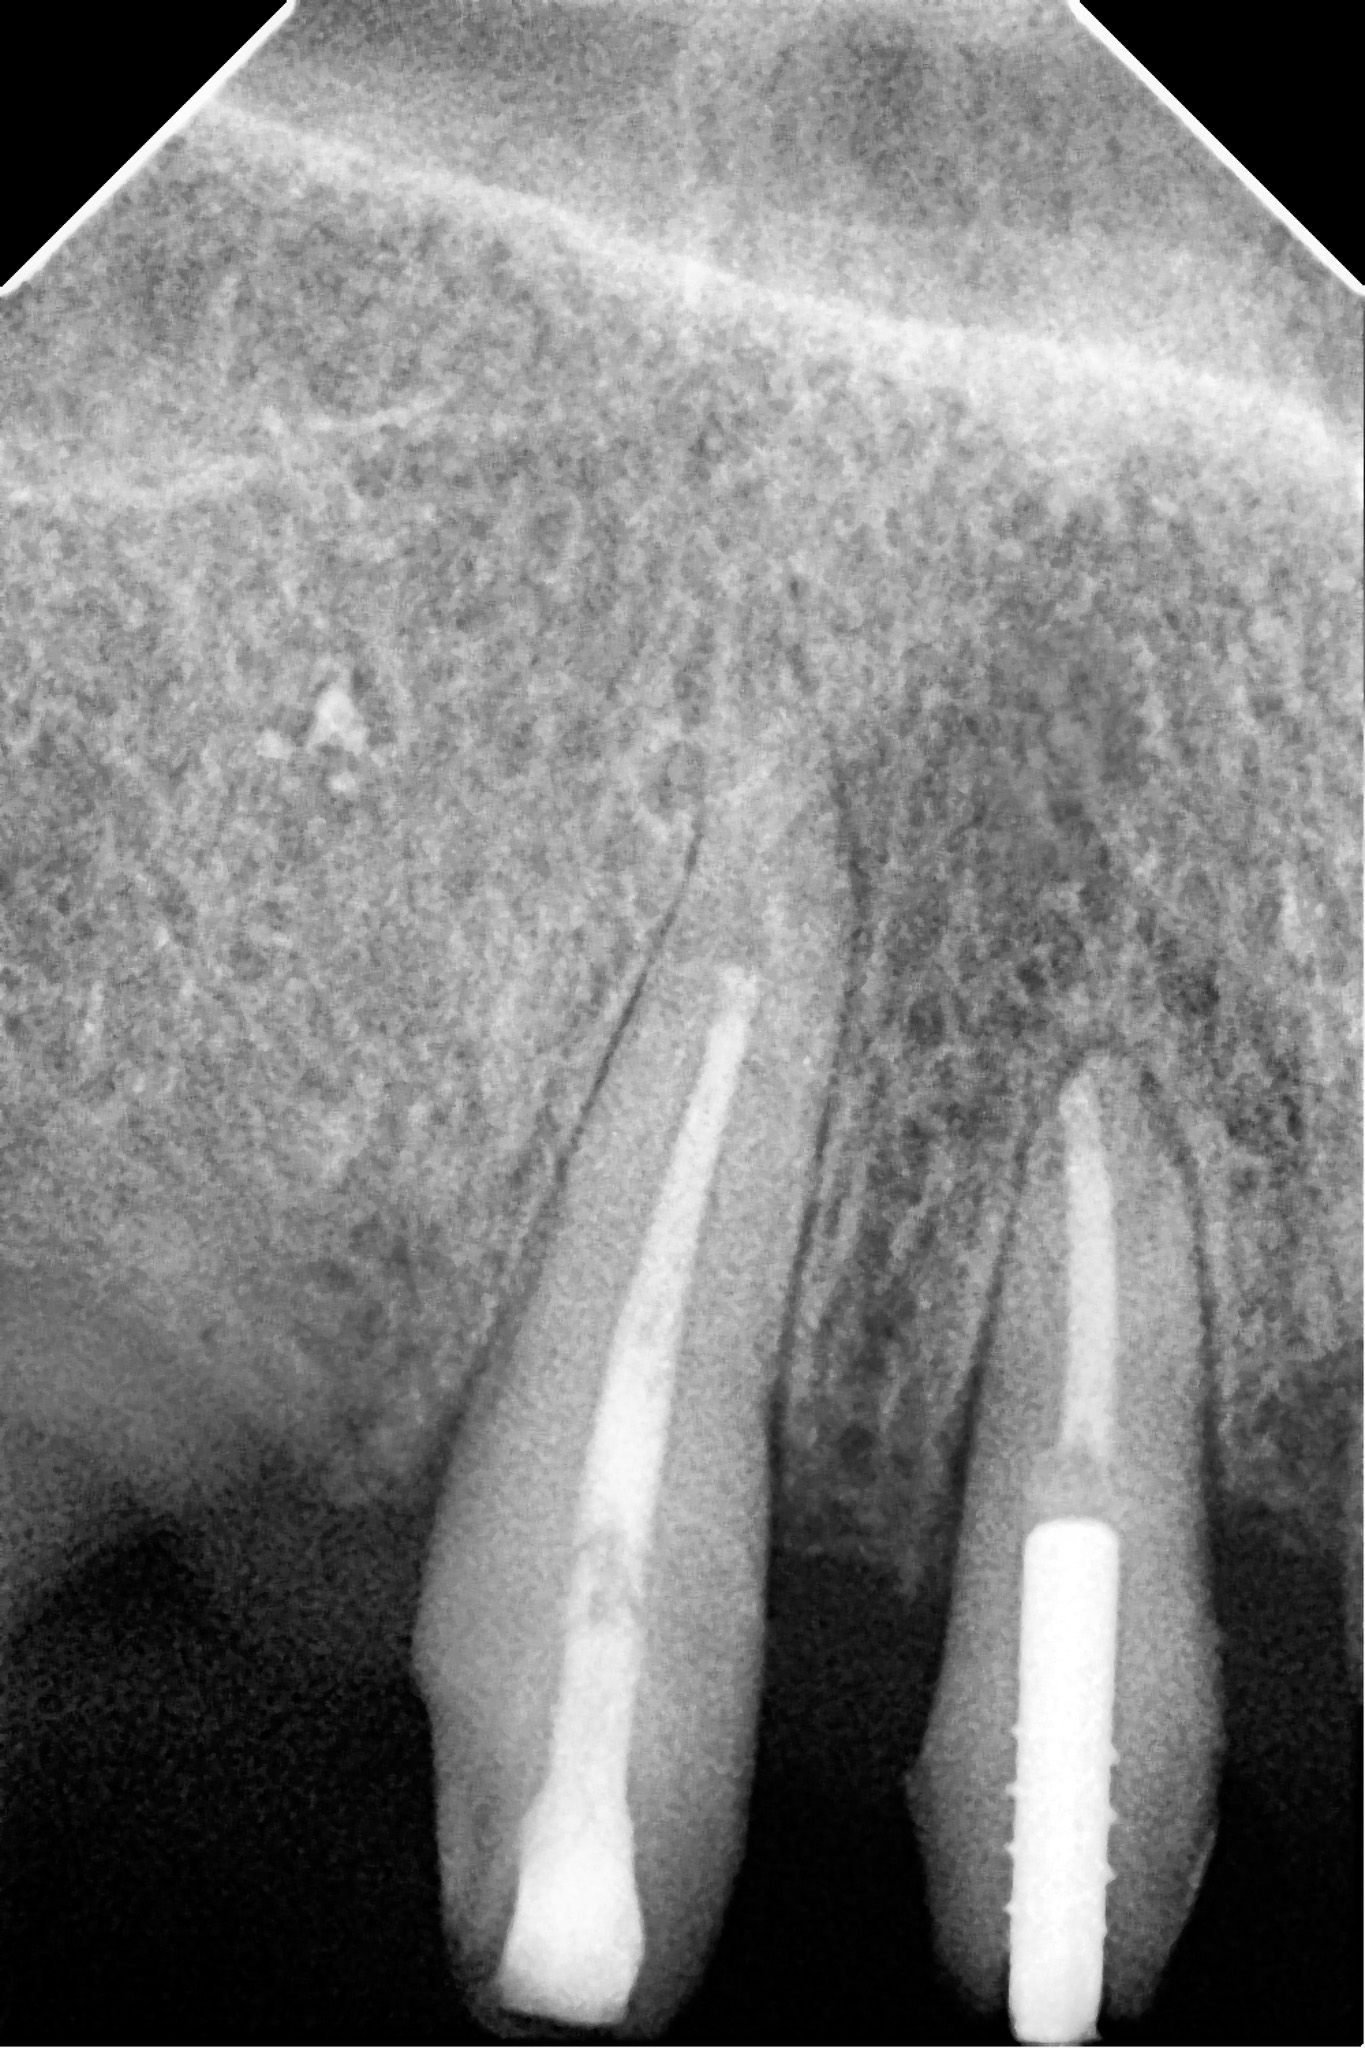

Pacjent zgłosił się do gabinetu w celu zaopatrzenia złamanego zęba (kła) w koronę protetyczną. W badaniu radiologicznym widoczna jest resorpcja materiału wypełniającego kanał po dawnym leczeniu endodontycznym oraz tworząca się zmiana zapalna w okolicy wierzchołka korzenia; z uwagi na konieczność wykorzystania zęba jako filar protetyczny przeprowadzono powtórne leczenie kanałowe (ReEndo) z wykorzystaniem nowoczesnych narzędzi rotacyjnych oraz mikroskopu zabiegowego. Kanał wypełniono szczelnie techniką obturacji płynną falą gutaperki (wypełnienie na ciepło).

Ząb posłużył do stabilnej odbudowy protetycznej.